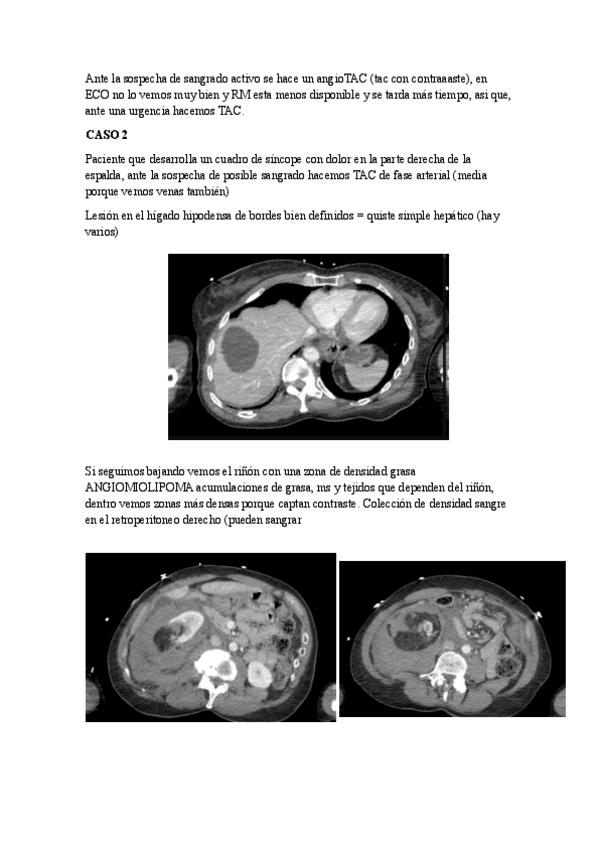

bazo.pdf